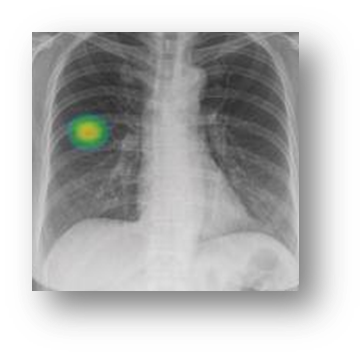

폐결절 CT 검사 방법

폐결절을 정확히 진단하기 위해서는 CT 검사가 필수적이에요. 저선량 흉부 CT는 방사선 노출을 최소화하면서도 결절을 발견할 수 있어요. 특히 정기 검진이나 추적 관찰에 많이 사용된답니다.

필요에 따라 조영제를 사용하는 CT 검사도 있어요. 조영제를 사용하면 결절의 혈류나 조직 특성을 더 자세히 알 수 있어요. 하지만 조영제 알레르기가 있는 분들은 주의해야 해요.